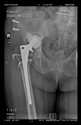

The guiding wire was inserted and controlled with fluoroscopy flashes (Figure 4). The drilling and reaming were carried out in accordance with the recommendations:

Figure 4.

The biocompatible aiming device after insertion of the guiding wire.

In all the cases operated with the above-described targeting procedure, the stems of the cups remained between the cortical bone surfaces without perforation of the linea terminalis, as shown by postoperative radiographs. There were no complicated surgical situations. In 16 cases, the wound healings were uneventful, and the hips were able to bear weight again after postoperative rehabilitation.